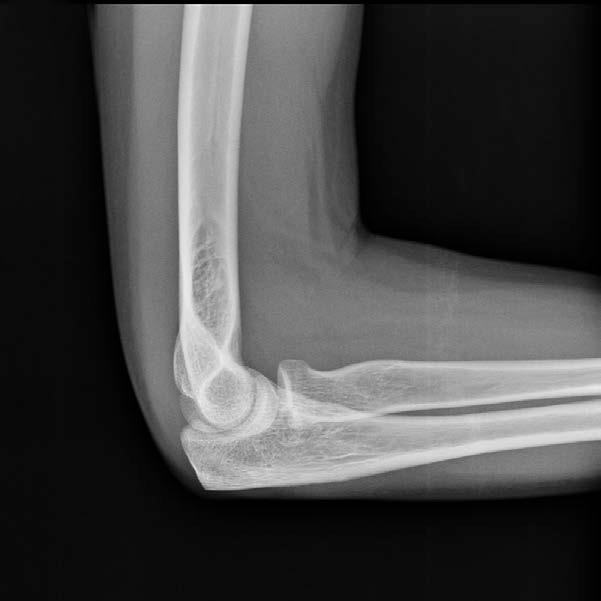

AudioLearn's Medical School Crash Courses presents Radiology

Written by experienced professors and professionally narrated for easy listening, this crash course is a valuable tool both during school and when preparing for the USMLE, or if you’re simply interested in the subject of Radiology.

The audio is focused and high-yield, covering the most important topics you might expect to learn in a typical Medical school Radiology course. Included are both capsule and detailed explanations of critical issues and topics you must know to master Radiology. The material is accurate, up to date and broken down into bite-sized sections. There are key takeaways following each chapter to drive home key points and quizzes to review commonly tested questions.